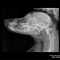

- Diferentemente do raio-x analógico, este raio-x oferece altíssima definição e todas as vantagens da tecnologia digital. É possível aproximar a imagem, trabalhar o contraste, exposição.O software permite ainda avaliações da medida cardíaca do animal e graus de displasia coxofemoral, por exemplo – explica o Dr. Nardeli Lucena.

- sofware com medidas para avaliações do tamanho cardíaco e medições dos ângulos de Norberg para diagnóstico e classificação de displasias coxofemorais;